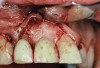

A 46-year-old man with an unremarkable medical history was referred for evaluation and treatment of the maxillary right central incisor implant. The implant, which had been placed 6 years prior, had never caused any problems until recently, when the patient noted both swelling and soreness at the site. Following 10 days of amoxicillin 500 mg tid, purulence was still present upon palpation of the tissue, and the patient was referred for consultation (Figure 6). Probing attachment loss of 10 mm on the distal aspect and 5 mm on the mesial were measured around the implant. Bone loss was advanced on the periapical radiograph at both the mesial and distal aspects of the hydroxyapatite-coated implant (Figure 7). Full-thickness facial and lingual flaps were reflected to access the implant and surrounding bone, with care taken to preserve the papilla. The defects around the implant on the mesial and distal were 1-wall, and bone loss was present on the direct facial and palatal aspects as well (Figure 8). The surface of the implant was decontaminated, followed by application of enamel matrix derivative. The lesion was filled with freeze-dried bone allograft (Figure 9). The graft-biologic was covered by a flowable polymer barrier (Figure 10). The flaps were coronally advanced and secured with monofilament sutures (Figure 11). The patient was prescribed amoxicillin with clavulanic acid and an oral rinse of 0.12% chlorhexidine during the post-operative period. The healing progressed uneventfully, achieving both a favorable soft-tissue profile and substantial bone fill, as determined radiographically. These results were stable for 7 years (Figure 12 and Figure 13).

Figure 8  Flap reflection revealed circumferential bone loss.

Figure 8